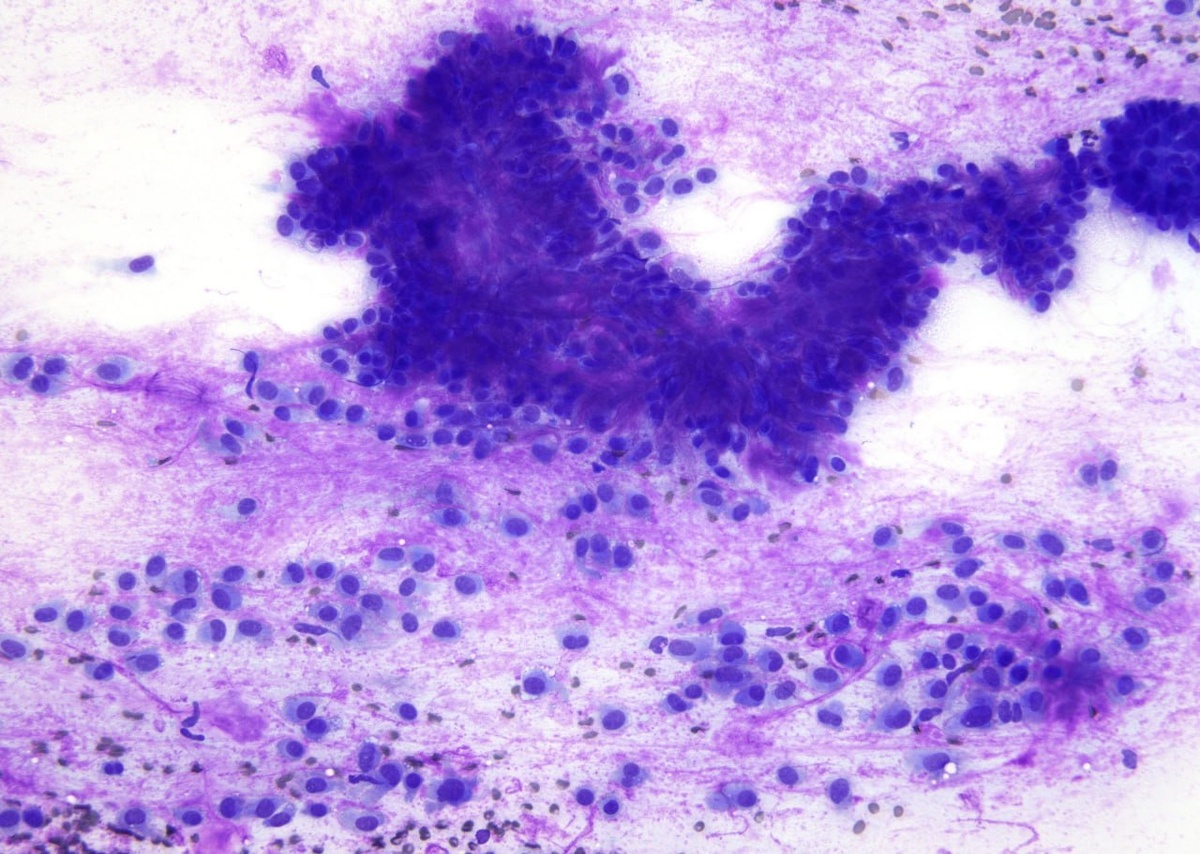

Классическая картина плеоморфной аденомы слюнной железы При качественном окрашивании по Романовскому-Гимзе миоэпителиальные клетки всегда ярко выделяются на фоне зернистой стромы. #слюннаяжелеза #цитология

Классическая картина плеоморфной аденомы слюнной железы

При качественном окрашивании по Романовскому-Гимзе миоэпителиальные клетки всегда ярко выделяются на фоне зернистой стромы.